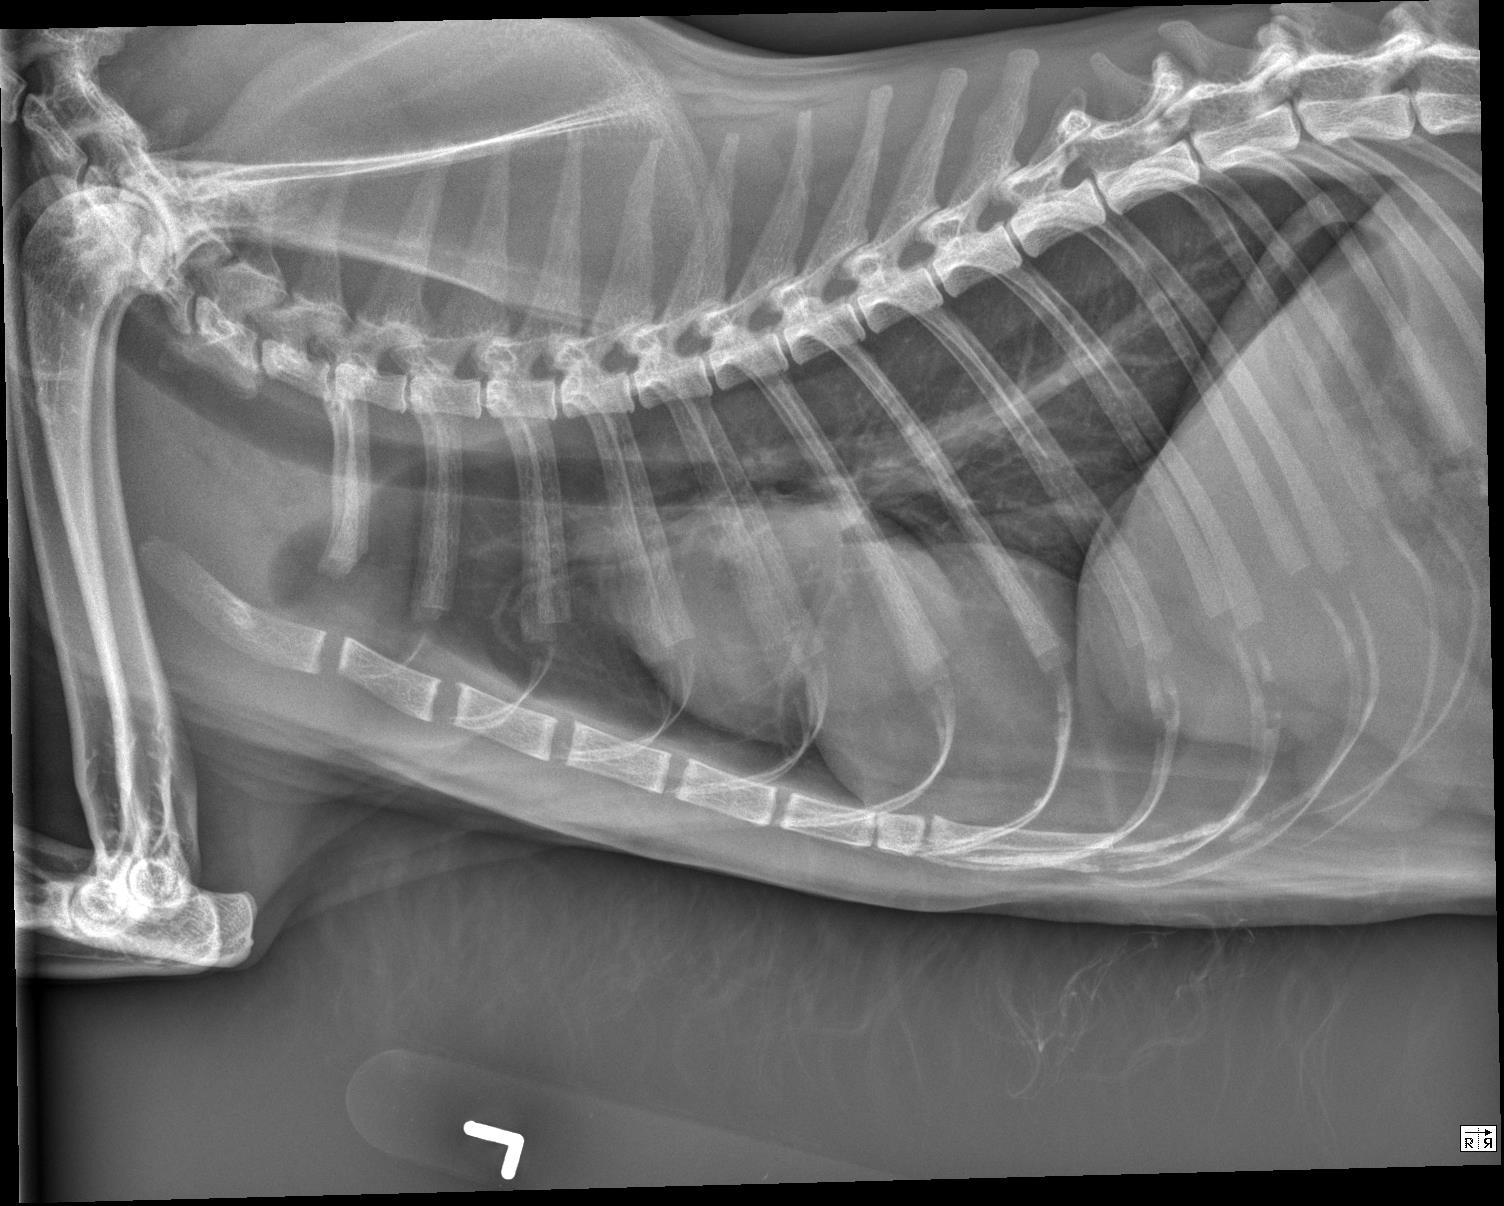

Orthogonal radiographs of the thorax are available for interpretation.

Within the caudal ventral thorax, directly adjacent to the diaphragm, there is a large, round, smoothly marginated, fat opaque structure that is causing dorsal and leftward deviation of the cardiac silhouette. The margins of the cardiac silhouette are distinctly identified superimposed with this structure on the lateral views.

The cardiac silhouette is normal in size. The pulmonary vessels, pulmonary parenchyma, and pleural space are normal.

The rounded structure in the caudal ventral thorax is suspected to represent fat opaque material and may be due to herniation/eventration of falcifom fat.

On the annotated image the cardiac margin remains visible when superimposed with the caudal structure. This indicates that those two are not of the same opacity. Furthermore the caudal structure is slightly more radiolucent compared to the cardiac outline.